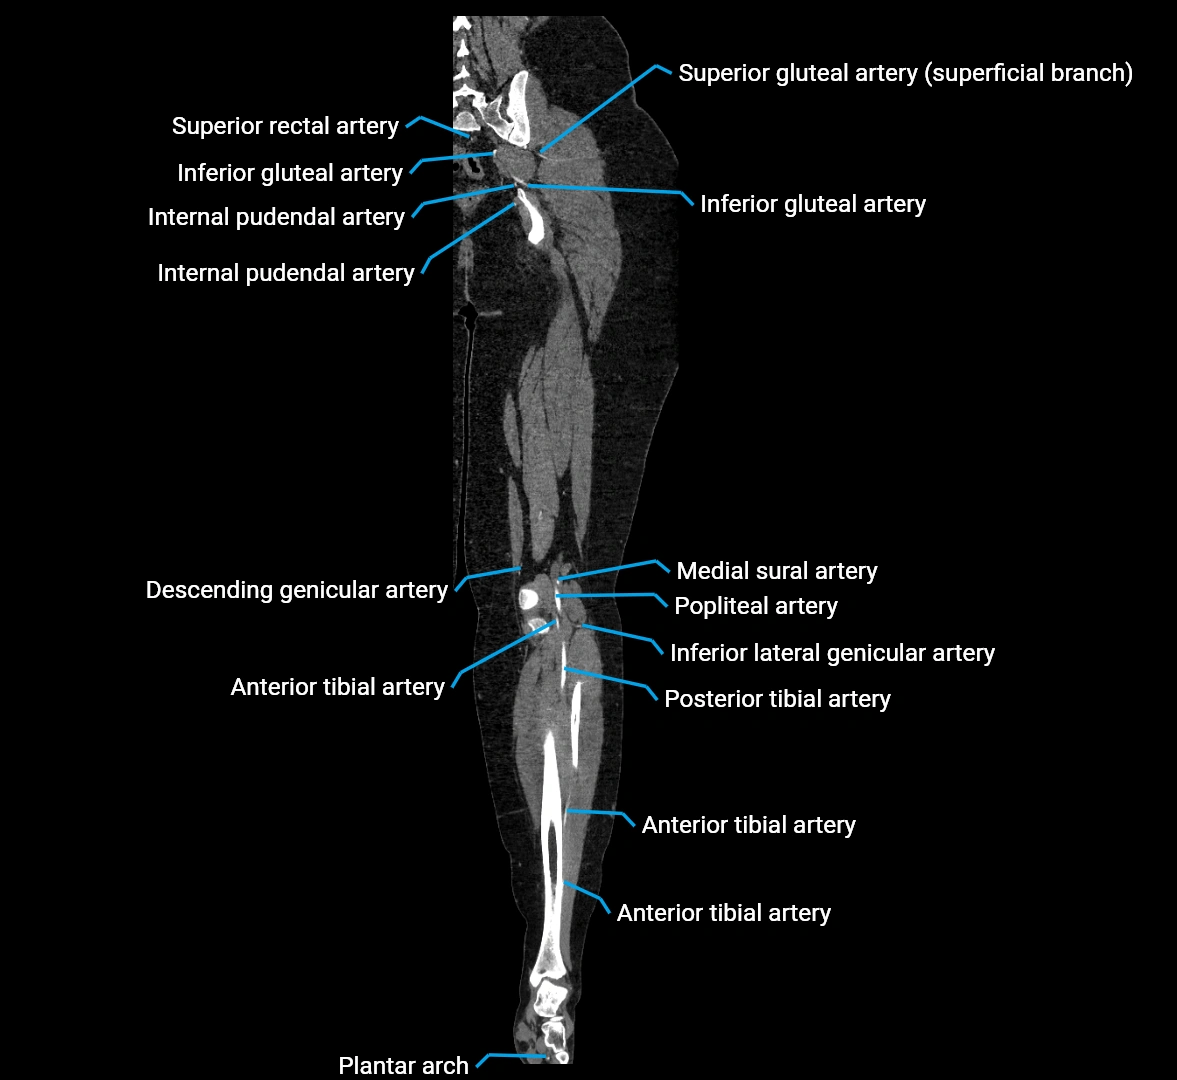

CT Appearance

Non-contrast CT:

• Appears as a tubular soft tissue structure anterior to vertebral bodies

• Calcified atherosclerotic plaques appear as hyperdense foci along the wall

• Useful for screening abdominal aortic aneurysm (AAA) size and mural calcification

Contrast-enhanced CT (CTA):

• Gold standard for abdominal aortic imaging

• Provides excellent detail of lumen, wall, aneurysm, thrombus, and branch vessels

• Multiplanar and 3D reconstructions help in aneurysm measurement, stent graft planning, and dissection evaluation

• Detects acute rupture, traumatic injury, or occlusion with high sensitivity